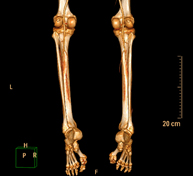

Exploració radiològica que mitjançant un sistema de raigs X i detectors que giren al voltant del pacient i que reconstrueixen les imatges per ordinador (TC Multidetector), permet calcular una sèrie de mesures a nivell de maluc, genolls i turmells per solucionar problemes de rotació i angulació de les extremitats inferiors. - TC d'ossos llargs

Exploració radiològica que mitjançant un sistema de raigs X i detectors que giren al voltant del pacient i que reconstrueixen les imatges per ordinador (TC Multidetector), permet l'estudi detallat dels ossos llargs (tíbia, peroné, fèmur, húmer, radi i cúbit). - Biòpsia òssia guiada per TC

Prova diagnòstica que consisteix en obtenir imatges de l'abdomen d'alta definició anatòmica (fetge, vesícula biliar, via biliar, pàncrees, melsa, estómac, intestins, ronyons, estructures vasculars, bufeta, úter i ovaris, etc.) mitjançant l'ús d'un equip de TC (Tomografia Computeritzada). Aquestes imatges s'estudien posteriorment en una estació de treball que permet reconstruccions bidimensional en diferents plans de l'espai, i també reconstruccions tridimensionals (3D: volumètriques). La majoria d'estudis requereixen l'ús de contrast iodat per millorar la definició de les imatges. - Lower leg rotational study using CT

Radiological examination based on an X-ray system and detectors that rotate around the patient, reconstructing the images by computer to calculate a series of measurements at the hips, knees and ankles with a view to solving problems affecting the rotation and angulation of the lower limbs.